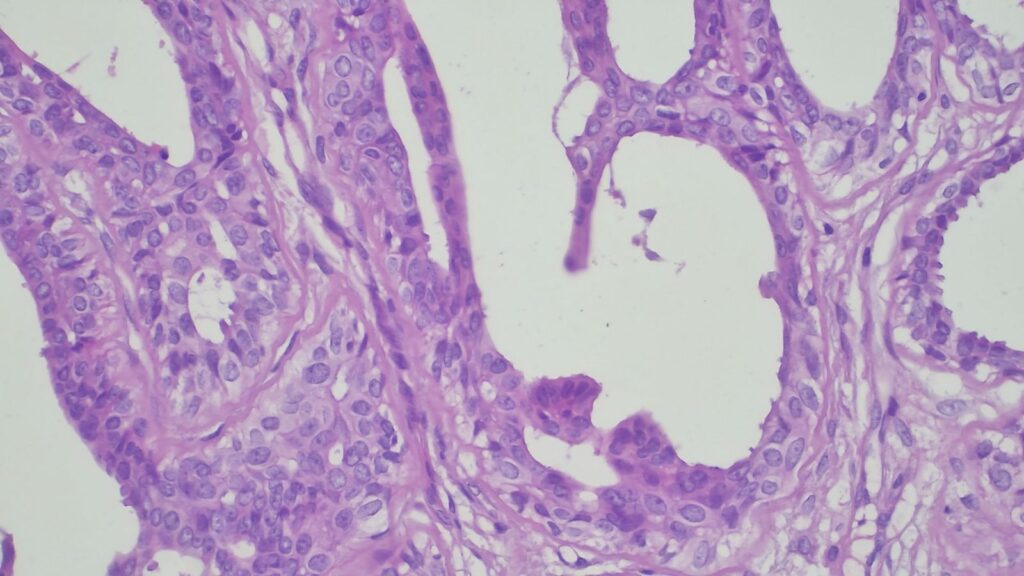

【病理形态学大解密:寻找良性证据】 仔细阅片后,专家指出了以下几个至关重要的形态学特征(见附带病理切片图):

✅ 腺体发育良好,呈圆形和分叶状结构。 ✅ 边缘虽略不规则,但整体呈推挤性(pushing)和局限性生长。 ✅ 无弥漫性浸润结构。 ✅ 无促结缔组织增生性间质反应(No desmoplastic stromal reaction,这是排除浸润癌的核心点)。 ✅ 细胞学形态温和(Bland cytology)。 ✅ 在慢性炎症和纤维化的背景下,仅见单个典型的核分裂象。 在病变外周,腺体表现出被瘢痕样间质压迫和塑形的特征,而不是破坏性或浸润性生长。